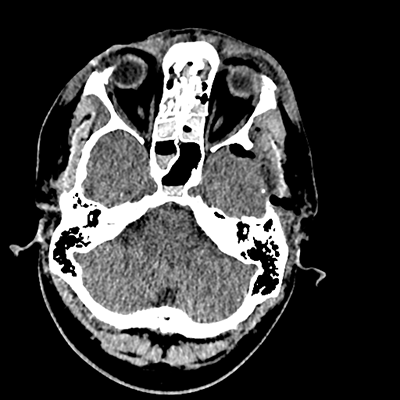

On day 5 of admission, he begins having intracranial hypertension again, spiking up to 40mmHg. You bolus with propofol and fentanyl, to no avail. You then push 30mL of 23.4% NaCl, which provides some brief improvement, allowing you to quickly get a non-contrast head CT. Unfortunately, he's now back up to 36mmHg. You review his labs, and note the following: Na 150, K 3.8, Cl 119, HCO3 18, BUN 21, Cr 0.85, glucose 136, sOsm 320.

NCHCT

NCHCT 1/20 1/20

NCHCT 2/20 2/20